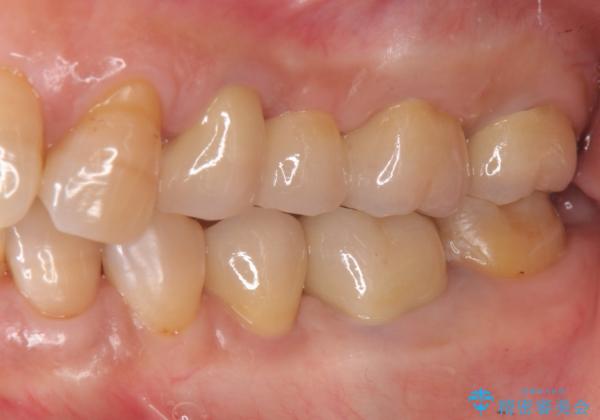

- 20年前に治療した銀歯が壊れ、審美的な修復を希望され来院されました。

銀歯・虫歯を除去し、ジルコニアを咬合再構成を行います。

- 66万円(仮歯・ジルコニアクラウン×6)費用は治療当時の料金となります

ジルコニアクラウンは補綴治療を行う上で、審美的かつ強度を備えたクラウンです。